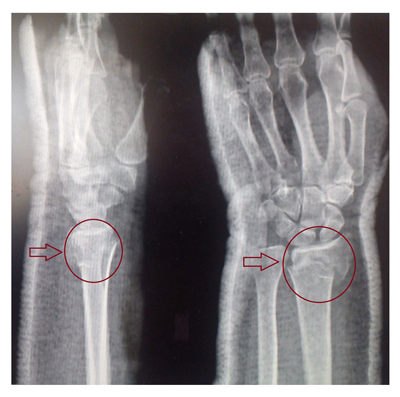

Диагноз «перелом лучевой кости» устанавливается на основе тщательного сбора анамнеза, который включает информацию о наличии травмирующего воздействия. Важным этапом является физикальное обследование, в ходе которого врач обращает внимание на такие симптомы, как боль и отек в области предплечья, вынужденное положение руки, деформация предплечья, укорочение конечности, патологическая подвижность и крепитация отломков. Также необходимо провести инструментальное обследование, включая рентгенографию в различных проекциях, что позволяет детально оценить характер и степень тяжести перелома, включая его локализацию, наличие смещения, а также возможные внутрисуставные повреждения и сопутствующие переломы локтевой кости.

В некоторых случаях для более надежной фиксации отломков кости применяют чрезкожную фиксацию спицами (закрытый остеосинтез), с обязательным проведением контрольной рентгенографии. Срок срастания при переломе лучевой кости зависит от множества факторов, включая точность репозиции и индивидуальные особенности организма, и в среднем составляет 4-5 недель. Если репозиция оказалась неудачной, может потребоваться повторное вправление, что увеличивает время срастания.